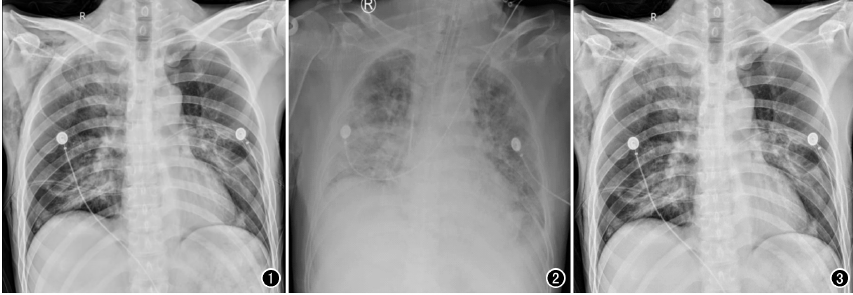

以心脏手术为例,开胸心脏手术多数是在低温、全麻和体外循环下进行,胸腔创伤较大、风险极高,心脏术后,心外科医师为了能及时了解术后患者的双肺复张情况、气管插管导管头端位置以及手术并发症等情况,需要及时对患者进行胸部X线片检查,以便观察气管插管位置,一般来说,插管位置下端应位于第3胸椎水平,过深或者过浅都将影响呼吸机的辅助效果,应确保位置准确,以免影响通气状况。另外,包括对于相关手术并发症的检查,包括:胸腔积液、气胸、肺不张等常见问题,需要及时进行胸部X光检查。相较于几百万像素的移动DR,百微移动DR,在图像质量上显示更清晰,检查效率更高,更利于医生及时进行处置。